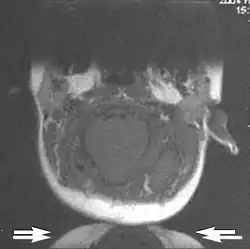

Fig. 3. Metal-related artifacts.[1]

Fig. 4. Metal-related artifacts.[1]

Metal artifacts occur at interfaces of tissues with different magnetic susceptibilities, which cause local magnetic fields to distort the external magnetic field. This distortion changes the precession frequency in the tissue leading to spatial mismapping of information. The degree of distortion depends on the type of metal (stainless steel having a greater distorting effect than titanium alloy), the type of interface (most striking effect at soft tissue-metal interfaces), pulse sequence and imaging parameters. Metal artifacts are caused by external ferromagnetics such as cobalt containing make-up, internal ferromagnetics such as surgical clips, spinal hardware and other orthopaedic devices, and in some cases, metallic objects swallowed by people with pica.[3] Manifestation of these artifacts is variable, including total signal loss, peripheral high signal and image distortion (Figs 3 and 4).[1] Reduction of these artifacts can be attempted by orientating the long axis of an implant or device parallel to the long axis of the external magnetic field, possible with mobile extremity imaging and an open magnet. Further methods used are choosing the appropriate frequency encoding direction, since metal artifacts are most pronounced in this direction, using smaller voxel sizes, fast imaging sequences, increased readout bandwidth and avoiding gradient-echo imaging when metal is present. A technique called MARS (metal artifact reduction sequence) applies an additional gradient, along the slice select gradient at the time the frequency encoding gradient is applied.